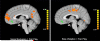

Social exclusion inherently involves an element of expectancy violation, in that we expect other people to follow the unwritten rule to include us in social interactions. In this functional magnetic resonance imaging (fMRI) study, we employed a unique modification of an interactive virtual ball-tossing game called "Cyberball" (Williams et al., 2000) and a novel paradigm called "Cybershape," in which rules are broken in the absence of social exclusion, to dissociate brain regions that process social exclusion from rule violations more generally. Our Cyberball game employed an alternating block design and removed evoked responses to events when the participant was throwing the ball in inclusion to make this condition comparable to exclusion, where participants did not throw. With these modifications, we replicated prior findings of ventral anterior cingulate cortex (vACC), insula, and posterior cingulate cortex activity evoked by social exclusion relative to inclusion. We also identified exclusion-evoked activity in the hippocampi, left ventrolateral prefrontal cortex, and left middle temporal gyrus. Comparing social exclusion and rule violation revealed a functional dissociation in the active neural systems as well as differential functional connectivity with vACC. Some overlap was observed in regions differentially modulated by social exclusion and rule violation, including the vACC and lateral parietal cortex. These overlapping brain regions showed different activation during social exclusion compared to rule violation, each relative to fair play. Comparing activation patterns to social exclusion and rule violation allowed for the dissociation of brain regions involved in the experience of exclusion versus expectancy violation.